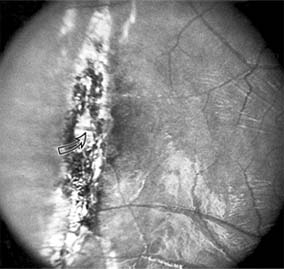

Presumed Ocular Histoplasmosis Syndrome (Figures 10-5, 10-6 and 10-7)

In this disease, serous and hemorrhagic detachments of the macula are associated with multiple peripheral atrophic chorioretinal scars and peripapillary chorioretinal scarring (see Chapter 7). The syndrome usually occurs in healthy patients between the third and sixth decades of life, and the scars are probably caused by an antecedent subclinical systemic infection with Histoplasma capsulatum. The macular detachments are due to subretinal neovascularization, and the visual prognosis depends on the proximity of the neovascular membrane to the center of the fovea. If the membrane extends inside the foveal avascular zone, only 15% of eyes will retain 20/40 vision. A macular scar may change over time, and 10% of patients with normal maculae will develop new atrophic scars in this region. The relative risk of developing macular subretinal neovascularization in the second eye of an affected patient is significant, and these patients should be instructed in the frequent use of the Amsler grid and the importance of prompt examination when changes are detected.

Figure 10-5

Figure 10-5: Presumed ocular histoplasmosis syndrome with active disease (large arrows) and an inactive pigmented macular scar (small arrow). Peripapillary pigmentation (curved arrow) is also present.

Figure 10-6

Figure 10-6: The early fluorescein angiogram shows an inactive hypofluorescent scar (small arrow) and the characteristic lacy hyperfluorescence of subretinal neovascularization (open arrows).

Figure 10-7

Figure 10-7: Late fluorescein leakage from macular subretinal neovascularization in a patient with presumed ocular histoplasmosis syndrome.